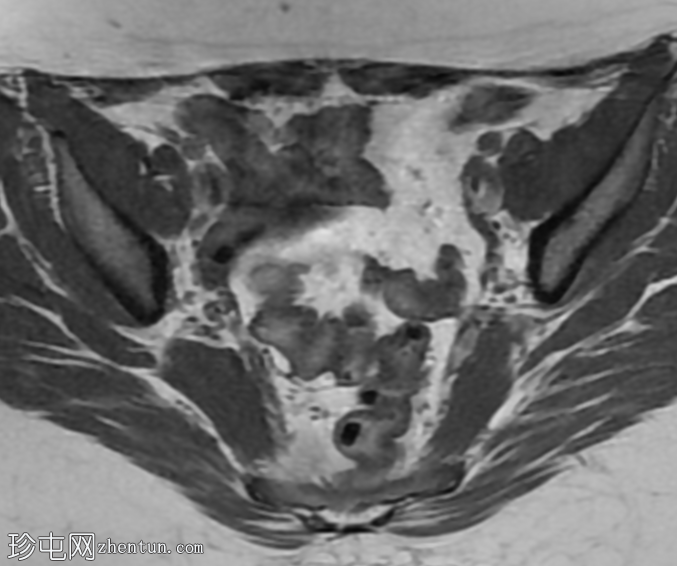

冠状位

T2加权像

子宫体积较小,最大横径、前后径和头尾径均为3.0 x 3.0 x 2.7 cm。子宫体与宫颈的比例为1.3:1。子宫无明显分区结构。

双侧卵巢发育不良,无卵泡活动。